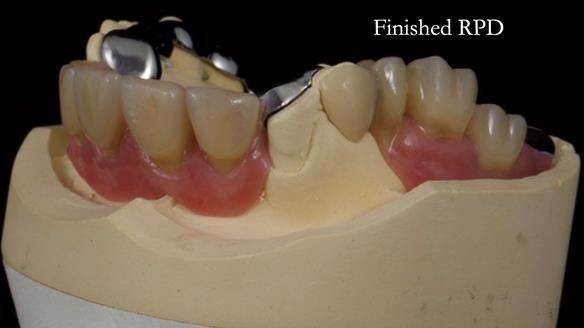

Keith’s case was one of the most challenging and rewarding cases I’ve treated this year. This 64 year old man presented with ill-fitting acrylic partial dentures that lacked stability, retention, and aesthetics. They constantly broke. He had lost the upper front teeth in a road traffic accident in his early 20s. The unopposed teeth had erupted, taking up space. After careful planning, we made a durable, metal-based upper partial denture/splint to address his dental concerns. He loved the outcome.

1. Denture design: A custom cobalt-chromium framework was Scandinavian-designed to maximise stability, protect the remaining teeth, and allow for future additions if needed.

Keith’s denture incorporated a Duracetal shell clasp on upper right first premolar (Myerson), which are designed to be virtually visible, providing a more aesthetic solution while enhancing patient comfort. The Scandinavian-inspired approach, based in modern removable prosthodontic techniques, ensured the denture was not only durable but also visually pleasing. Additionally, the design was carefully planned to allow for future modifications, ensuring that if Keith loses additional teeth, the denture can be adapted rather than replaced entirely.